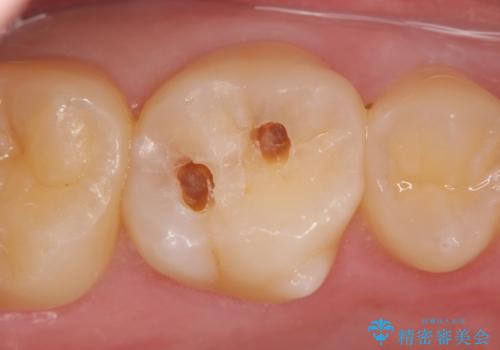

奥歯のインプラント治療

- 奥歯を失い噛めない、しっかりと噛めるようになりたいと希望され来院されました。

清掃性に優れたジルコニアカスタムアバットメント、ジルコニアクラウンを用いて機能性だけでなく審美性・予知性を高めます。

- 130万円(HAインプラント×3・骨造成・ジルコニアカスタムアバットメント×3・ジルコニアクラウン×4)費用は治療当時の料金となります